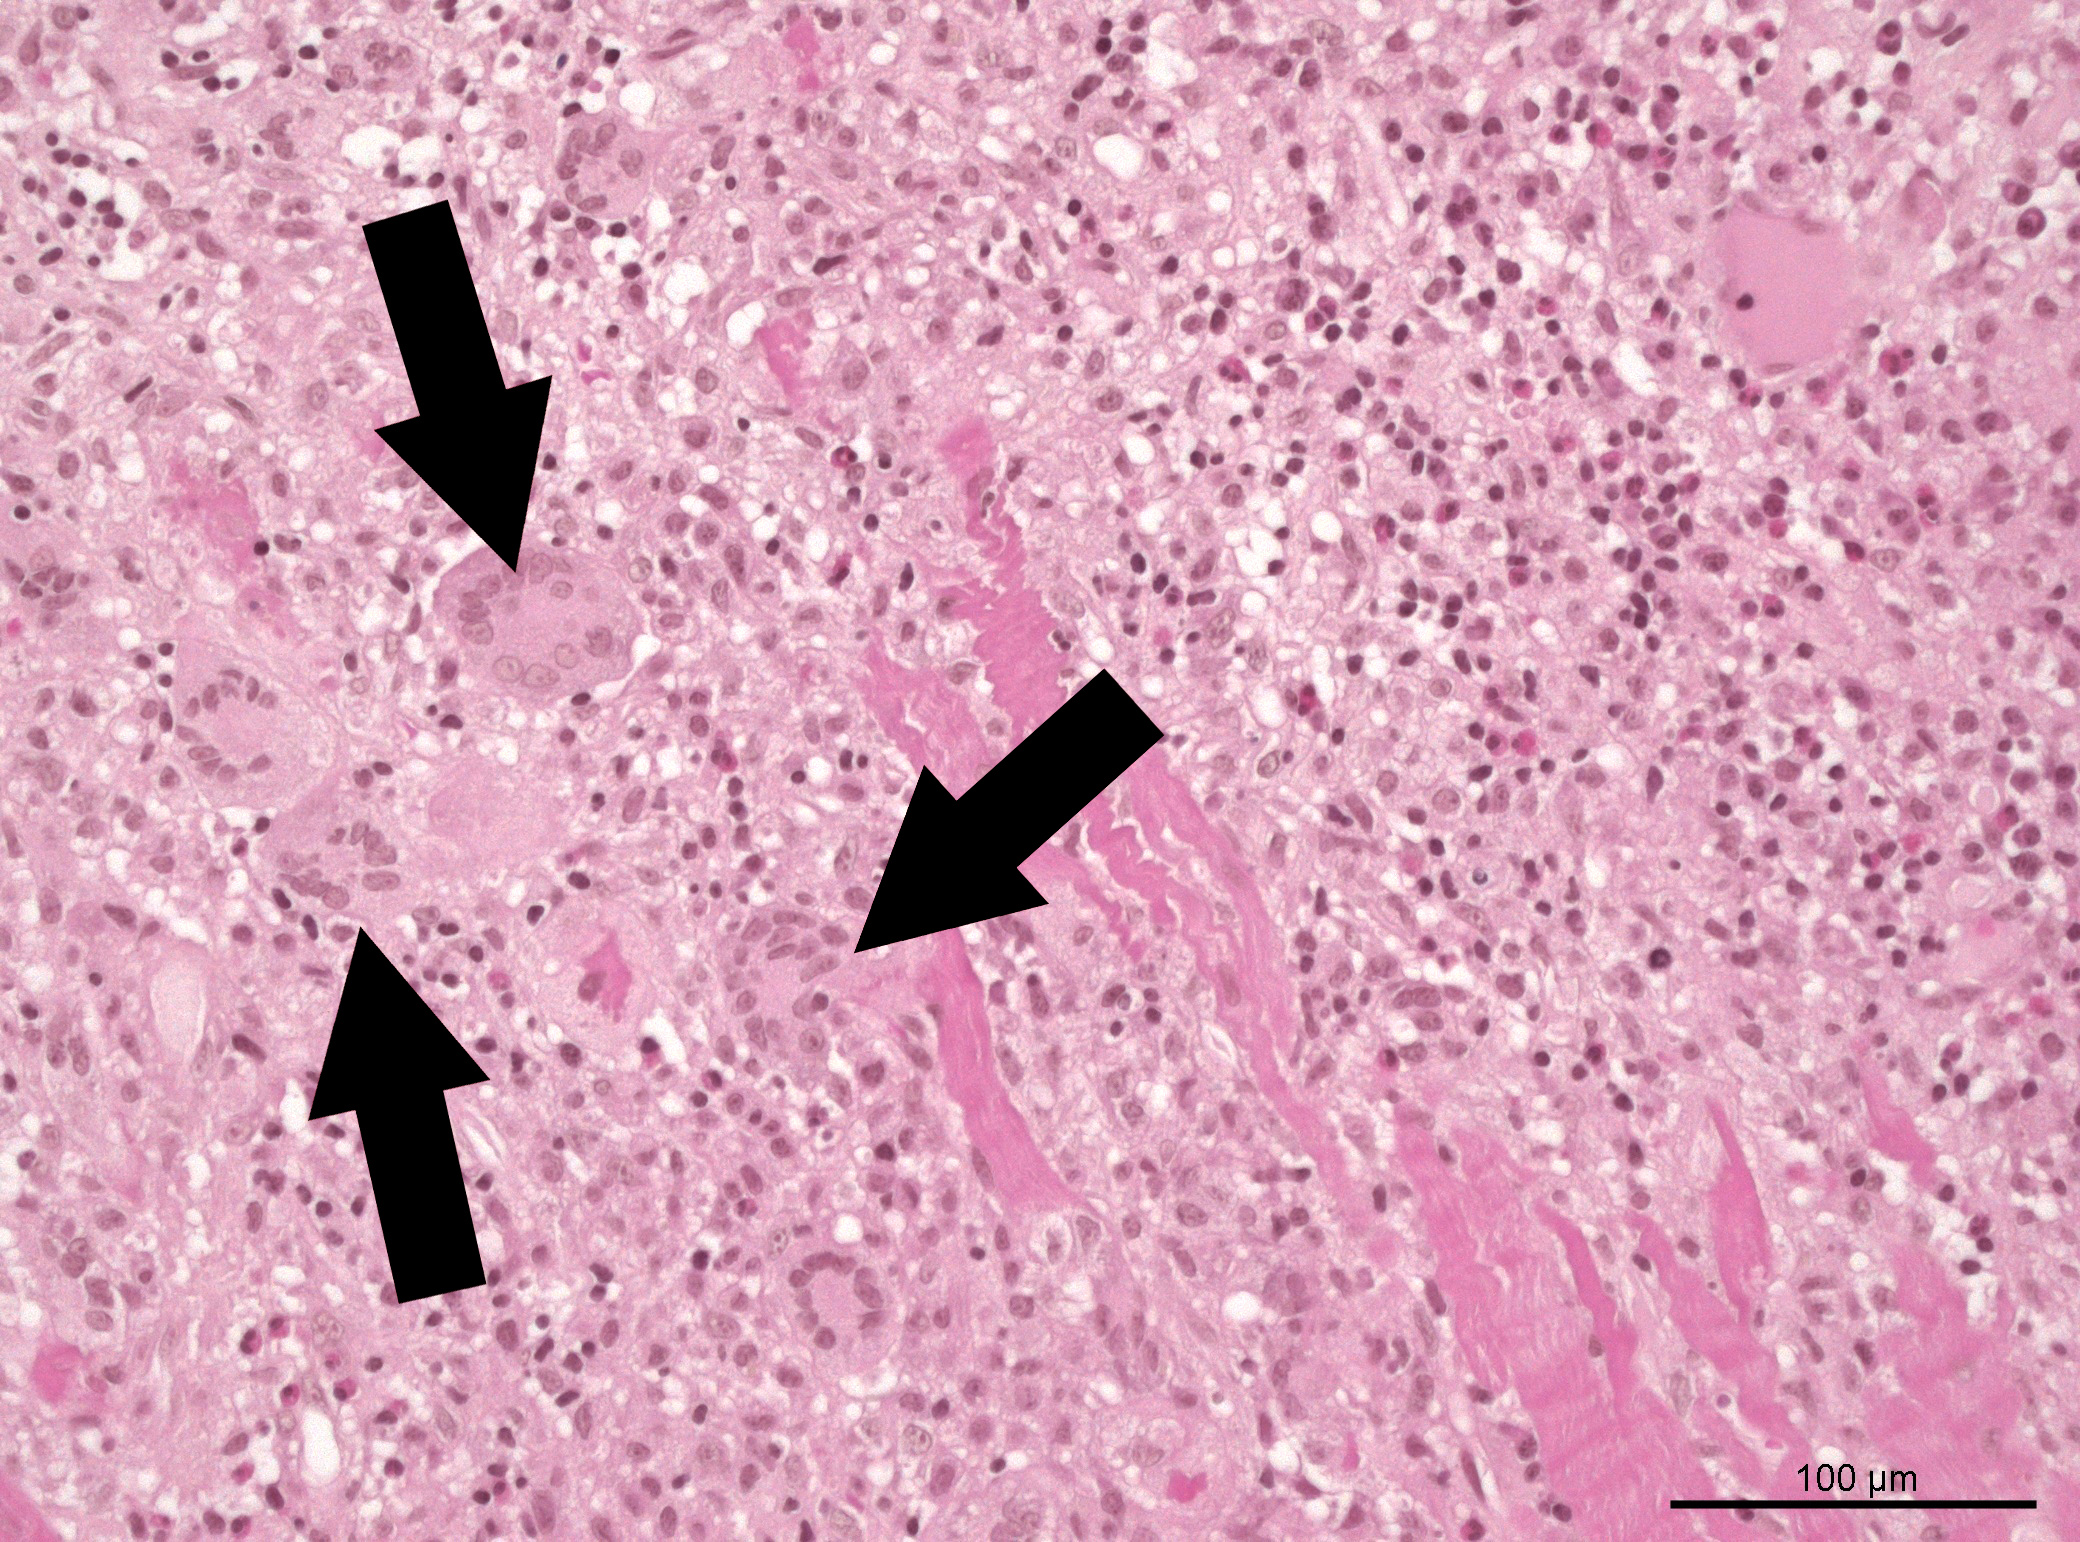

An important initial finding of the study is that patients with so-called giant cell myocarditis – a special form of the disease named after the very large cells found in tissue samples – have a significantly higher mortality rate (50 percent) as other subgroups (approximately 30 percent). These data point to the great importance of early tissue sampling for sample collection as a central aspect of the diagnosis of fulminant myocarditis.

"Early endomyocardial biopsy should be the goal in cases of clinically suspected fulminant myocarditis, as the histopathological findings play a decisive role in management and prognosis," adds Prof. Dr. Georg Nickenig, cardiologist and director of the UKB Heart Center. "This will enable us to improve therapeutic concepts and thus also treatment outcomes for all patients with fulminant myocarditis in the long term."